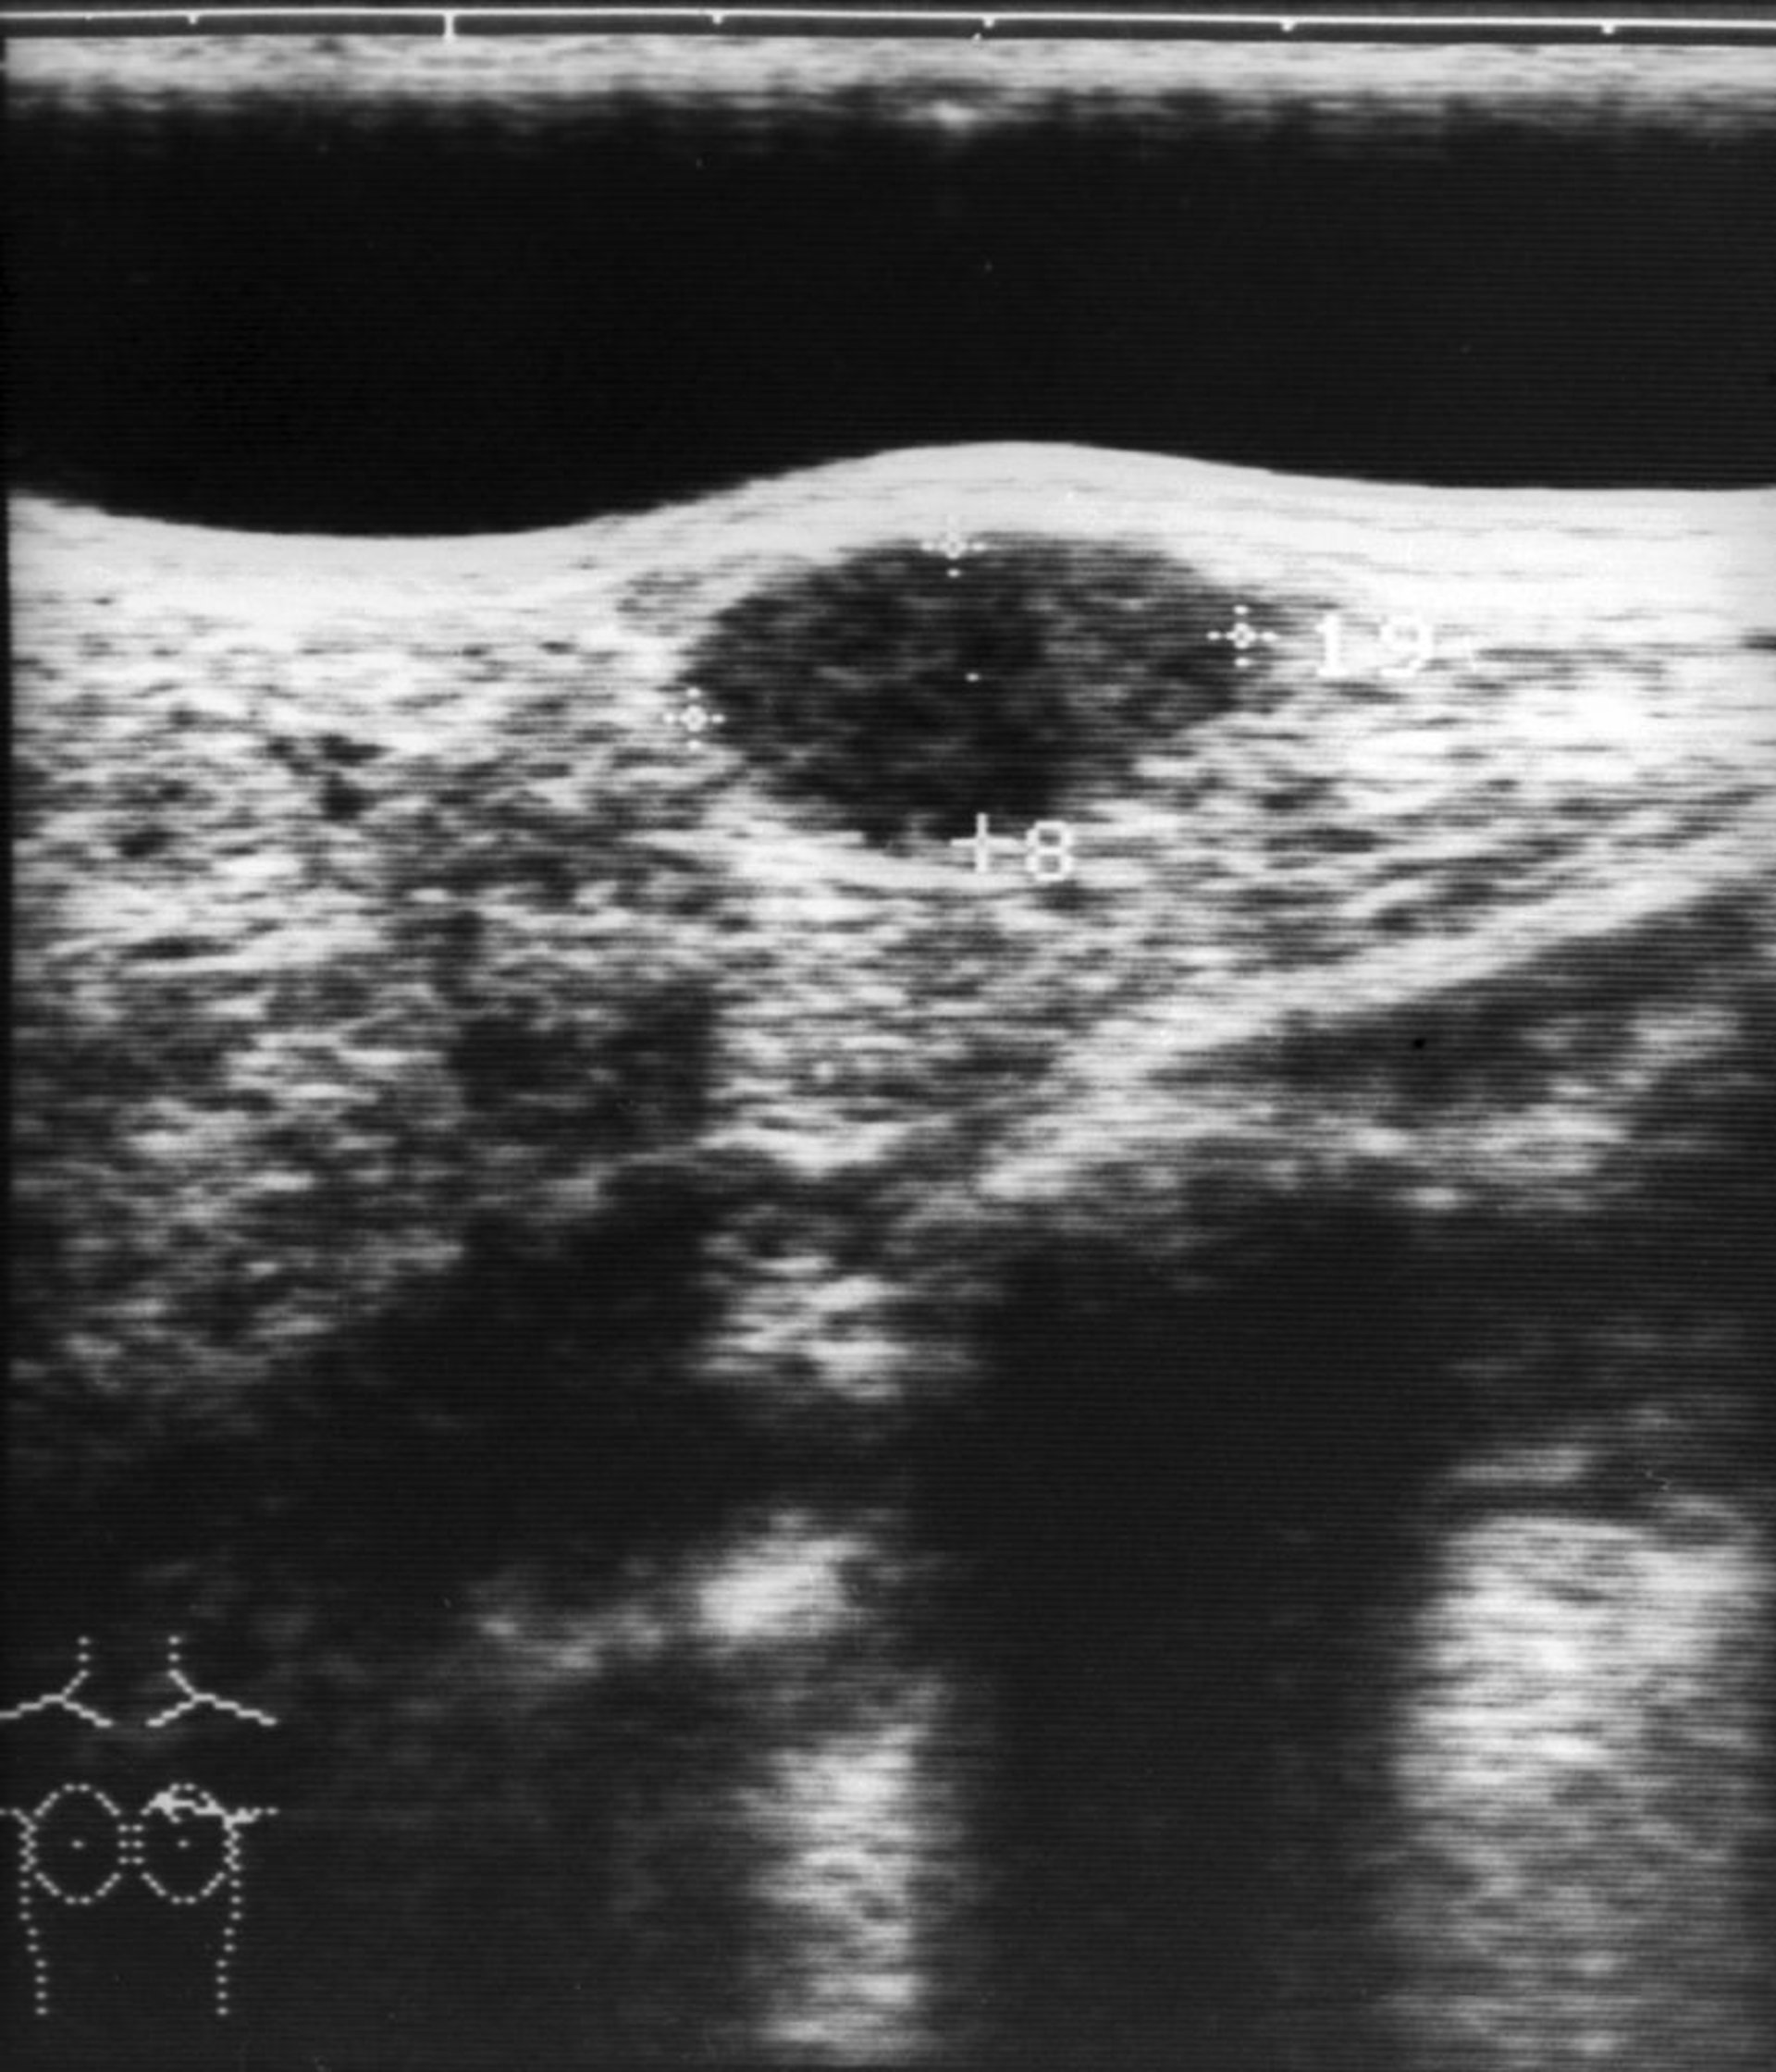

乳房のしこりの超音波所見

この画像には,超音波検査で描出された乳腺線維腺腫(画像中央上部の楕円形の低エコー構造)が写っている。